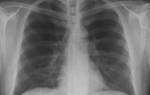

Рассмотрим для примера рентгеновский снимок легких в норме:

На нем визуализируется множество затемнений и просветлений (белого и черного цвета), которые могут запугать читателей. На самом деле эта рентгенограмма расшифровывается просто (см. следующий снимок)

На рентгенограмме подписаны все анатомические структуры, чтобы читателям было легко разобраться. Предлагаем запомнить интенсивность легочных полей. Норма не предполагает наличия патологических затемнений (белого цвета) и просветлений (темного цвета), которых нет на изображении.

Рентген здоровых легких описывать следует по классическому стандарту. Вначале вносятся записи о патологических рентгеновских синдромах, затем легочные поля, корни, купола диафрагмы, реберно-диафрагмальные синусы, сердечная тень и мягкие ткани.

Классический алгоритм описания здоровых легких:

- В легочных полях без видимых очаговых и инфильтративных теней;

- Корни не расширены, структурны;

- Контуры диафрагмы и реберно-диафрагмальные синусы без особенностей;

- Сердечная тень обычной конфигурации;

- Мягкие ткани без особенностей.

Вышеприведенная рентгенограмма подпадает под данное описание.